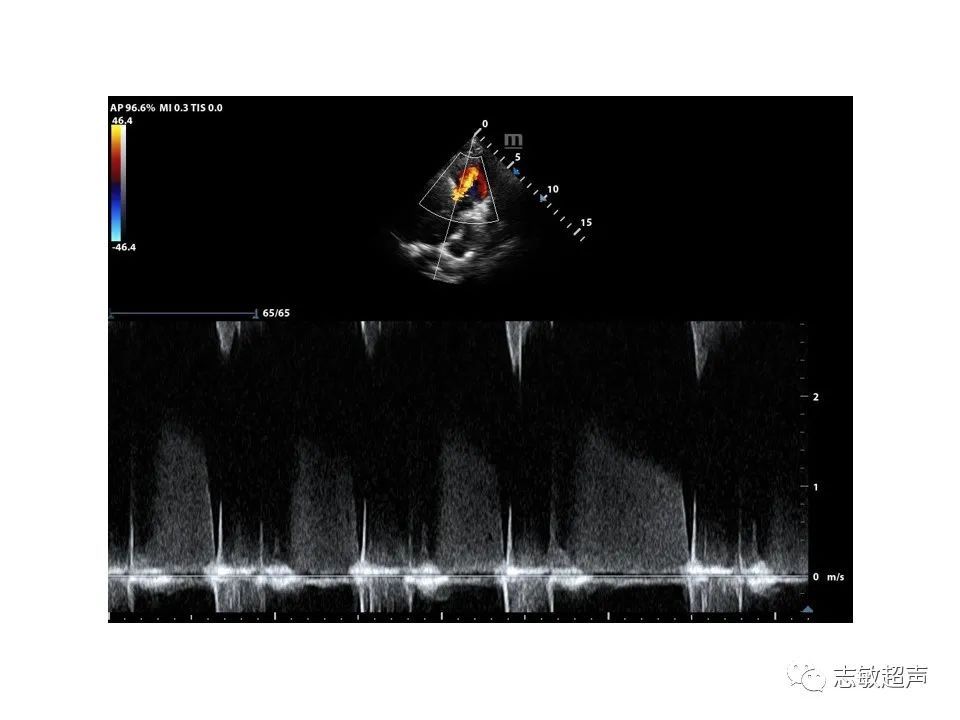

2.肺动脉主干内旋流